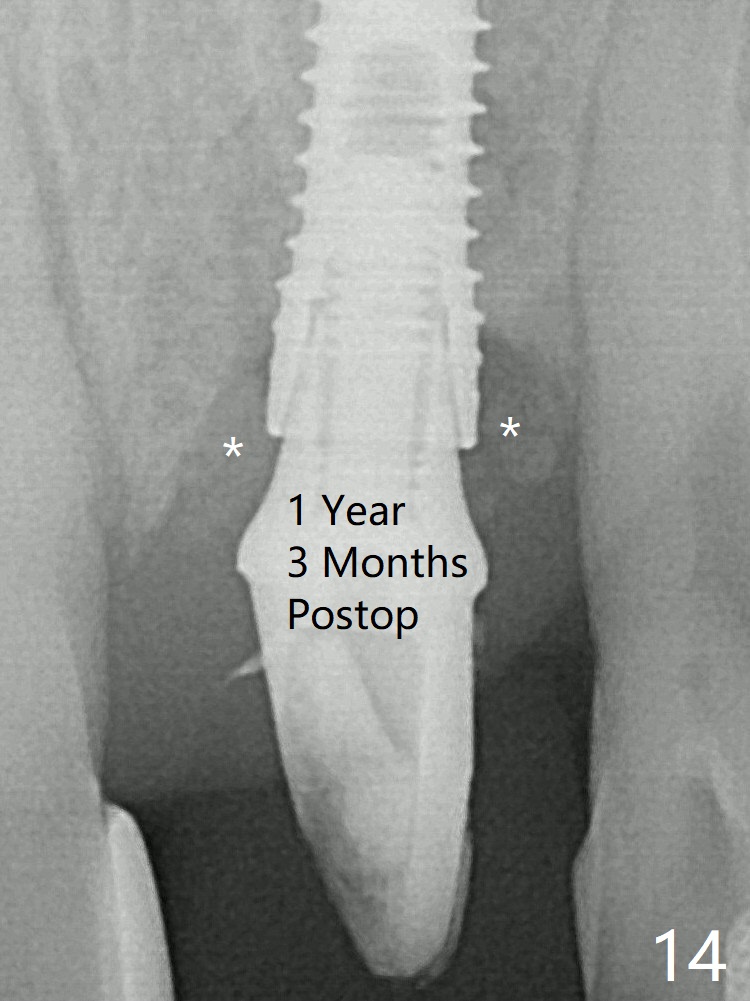

After placement of a 3.8x15 mm implant, PRF is laid against the inner surface of the buccal defect and allograft (Fig.5 *) is packed mainly in the buccal gap before and after insertion of a 4.5x5(4) mm abutment. The bone graft remains in place 3.5 and 4.5 months postop (Fig.11,12 *). Between 3 and 4 months postop, the mesial surface of the abutment has been trimmed (Fig.12 >). Since the mesial surface of the tooth #10 will be reduced (white curved line) to correct the upper dental midline, an angled abutment (red line) seems to be necessary to shift the provisional distal. The socket at UL1 seems to have healed except the most coronal 1 year 3 months postop (Fig.14 *).